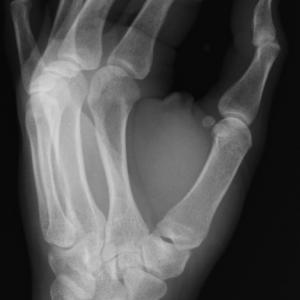

В началото на ноември той провежда опити с катодни лъчи в тръби на Ленард. Тръбата на Ленард е обвита в черна хартия, непропускаща видимата светлина, предизвиквана от катодните лъчи и излъчвана от областта около анода. Рьонтген забелязва, че намиращите се на известно разстояние от тръбата бариеви кристали светят в тъмнината. При изключено напрежение на тръбата кристалите не светели повече. Той поставя недалеч от тръбата екран, покрит с бариеви соли, които светвали всеки път, когато включвал напрежението и угасвали след изключването му. Ученият започва да експериментира с различни материали между тръбата и екрана. Картонът, хартията и ебонитът не влияели на яркостта на светене, докато металните предмети хвърляли сянка върху екрана. Той поставя дланта си на пътя на Х-лъчите и на екрана се появява изображение на костите. Меките тъкани обаче се оказват прозрачни за тях.